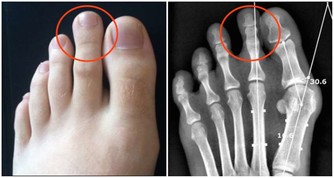

而且,這種對膝蓋的磨損是不可修復的!磨損如果過度嚴重,只能夠置換關節!

因為膝關節的壽命由基因決定,是60年,過度使用會加重對它的磨損,並且不可修復。

尤其是蹲下去再站起來,對關節的磨損最大。關節軟骨大概有1到2毫米,作用就是緩衝壓力,保護骨骼不破裂。

在爬山和爬樓梯的時候,膝關節會承受超過本身體重3到4倍的壓力。

尤其是50歲以後,人的膝關節多少都會有些磨損的情況,此時,就要減少此類運動。